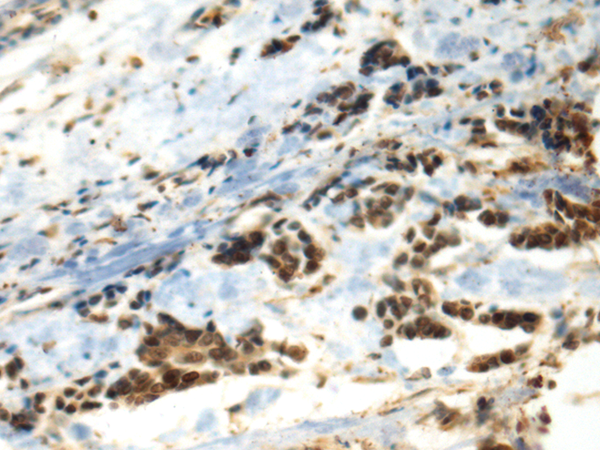

The image is immunohistochemistry of paraffin-embedded Human breast cancer tissue using (Antibody) at dilution 1/70.

The image is immunohistochemistry of paraffin-embedded Human thyroid cancer tissue using (Antibody) at dilution 1/70.